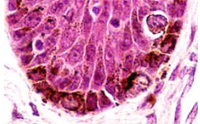

研究小組向人體皮膚細(xì)胞植入3個(gè)基因,培養(yǎng)生成誘導(dǎo)多功能干細(xì)胞,并培育出名為“胚狀體(EB)”的細(xì)胞團(tuán)塊。接著,研究人員向胚狀體植入人體制造色素細(xì)胞時(shí)所必需的成分,培育兩個(gè)月左右,結(jié)果獲得的細(xì)胞中有60%至70%是人體色素細(xì)胞。

色素細(xì)胞存在于人體皮膚等處,能夠制造黑色素,防止人體遭受紫外線傷害。色素細(xì)胞如果出現(xiàn)癌變,就會(huì)患上惡性黑色素瘤等,而出現(xiàn)皮膚變白癥狀的白癜風(fēng)和白化病以及白發(fā)等均被認(rèn)為是色素細(xì)胞減少造成的。研究小組認(rèn)為,新成果將有助于弄清上述疾病的致病原因,并且在制藥和制作人造皮膚等再生醫(yī)療中得到應(yīng)用。

Epidermal melanocytes play an important role in protecting the skin from UV rays, and their functional impairment results in pigment disorders. Additionally, melanomas are considered to arise from mutations that accumulate in melanocyte stem cells. The mechanisms underlying melanocyte differentiation and the defining characteristics of melanocyte stem cells in humans are, however, largely unknown. In the present study, we set out to generate melanocytes from human iPS cells in vitro, leading to a preliminary investigation of the mechanisms of human melanocyte differentiation. We generated iPS cell lines from human dermal fibroblasts using the Yamanaka factors (SOX2, OCT3/4, and KLF4, with or without c-MYC). These iPS cell lines were subsequently used to form embryoid bodies (EBs) and then differentiated into melanocytes via culture supplementation with Wnt3a, SCF, and ET-3. Seven weeks after inducing differentiation, pigmented cells expressing melanocyte markers such as MITF, tyrosinase, SILV, and TYRP1, were detected. Melanosomes were identified in these pigmented cells by electron microscopy, and global gene expression profiling of the pigmented cells showed a high similarity to that of human primary foreskin-derived melanocytes, suggesting the successful generation of melanocytes from iPS cells. This in vitro differentiation system should prove useful for understanding human melanocyte biology and revealing the mechanism of various pigment cell disorders, including melanoma.